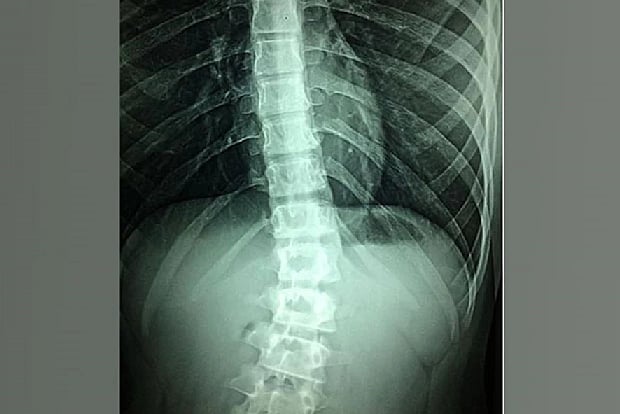

Representative image

San Diego: According to a new study, chronic pain spinal cord stimulation (SCS) uses an implanted device to supply a small amount of electricity directly to the spinal cord, altering or blocking nerve activity and minimizing the sensation of pain reaching the brain. The findings of the research were published in the journal 'Bioelectronic Medicine', a research team led by scientists at the University of California San Diego School of Medicine.